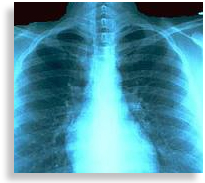

Radiography is mostly the modern medical technology used to diagnose the ailment and diseases of the internal parts of the body using X-ray, Fluoroscopy, Ultrasound, CTscan, MRI, Angiography and PET technologies. It helps in getting a detailed image of internal body parts and their functioning. By using this, a doctor can easily diagnose the disease and can suggest effective treatment procedure. There are two types of radiography: diagnostic and therapeutic. Diagnostic radiography is concerned with operating radio imaging machines and interpreting results. But therapeutic radiography involves treatment of cancers, ulcer and tumors with the help of radiation technology. Correct diagnosis is important for providing exact treatment for a disease.For some ailments it is not possible to find out the diseases by the symptoms alone.

PET is a nuclear medicine medical imaging, a branch of medicine and medical imaging that uses unsealed radioactive substances in diagnosis and therapy, which produces a three dimensional image of the functional processes in the body.Unless we get a detailed image of internal body parts and what is happening in the body the treatment will not be effective. Radiography is mainly concerned with operating radio imaging machines such as X-ray and interpreting results.

It also involves treatment of cancers and tumors with radiation. There are two career choices in the field- Diagnostic Radiography and Therapeutic Radiography. The main responsibility of the Diagnostic radiographer is to explain the procedure to the patients, prepare them for the tests and operate the machine, and do the maintenance of equipment and records. They also assist physicians in performing procedures such as Myelograms (an exam to detect injuries, Cysts or tumours in the spinal cord) and surgeons in the operating room with portable x-ray machines or fluoroscopic machines.Therapeutic radiography or Radiotherapy is now being used in the treatment and diagnosis of a large number of diseases, including cancer, tumors and ulcers. A therapy radiographer uses radiation in highly controlled conditions in the treatment of tumor. Exact amount of radiation will shrink the tumour. The need for professionals in the field of radiography is increasing. A radiographer is also called Radiologic technologist who has to handle the equipments and upgrade their skills now and then as technology advances. As more sophisticated newer machines are coming up and experts in this career is less, there is an increase in the need for radiographers.